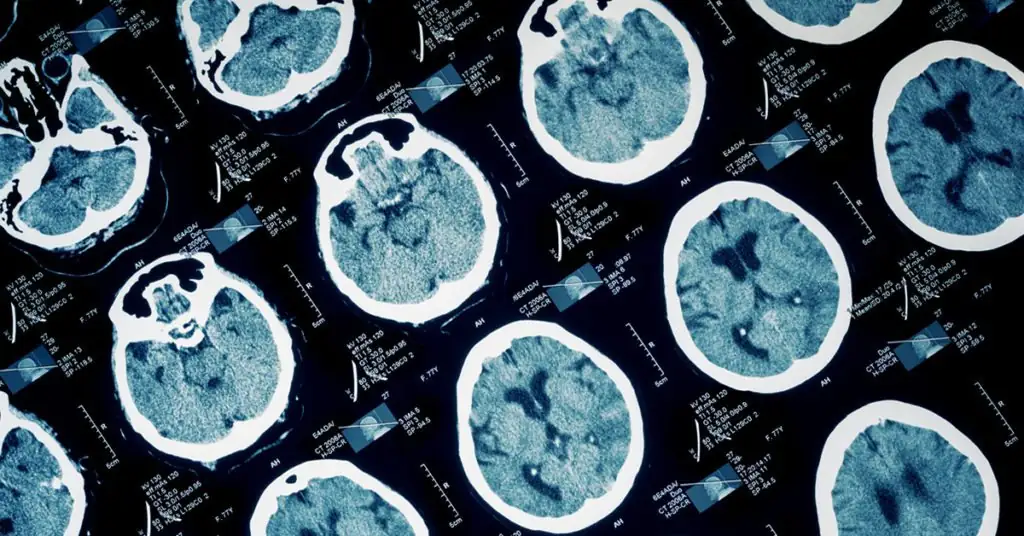

What is Anoxic Brain Injury?

An anoxic brain injury is a serious injury that can cause severe cognitive problems and disabilities and results from a lack of oxygen to the brain. Anoxic brain injury can be life-threatening and occurs when the oxygen to the brain is significantly low for at least four minutes. The longer the brain is without the oxygen it needs, the more severe and widespread the damage will be. This lack of oxygen will lead to anoxic brain damage where the oxygen-deprived cells begin to die.